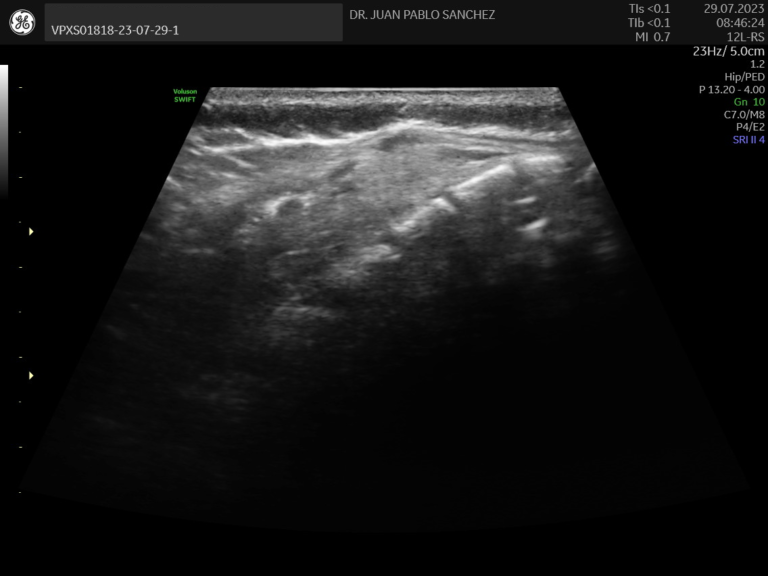

Ecografia de caderas

Estudio esencial en bebés para detectar displasia del desarrollo de cadera. Es indolora y se realiza idealmente en los primeros meses de vida como parte del control del niño sano.